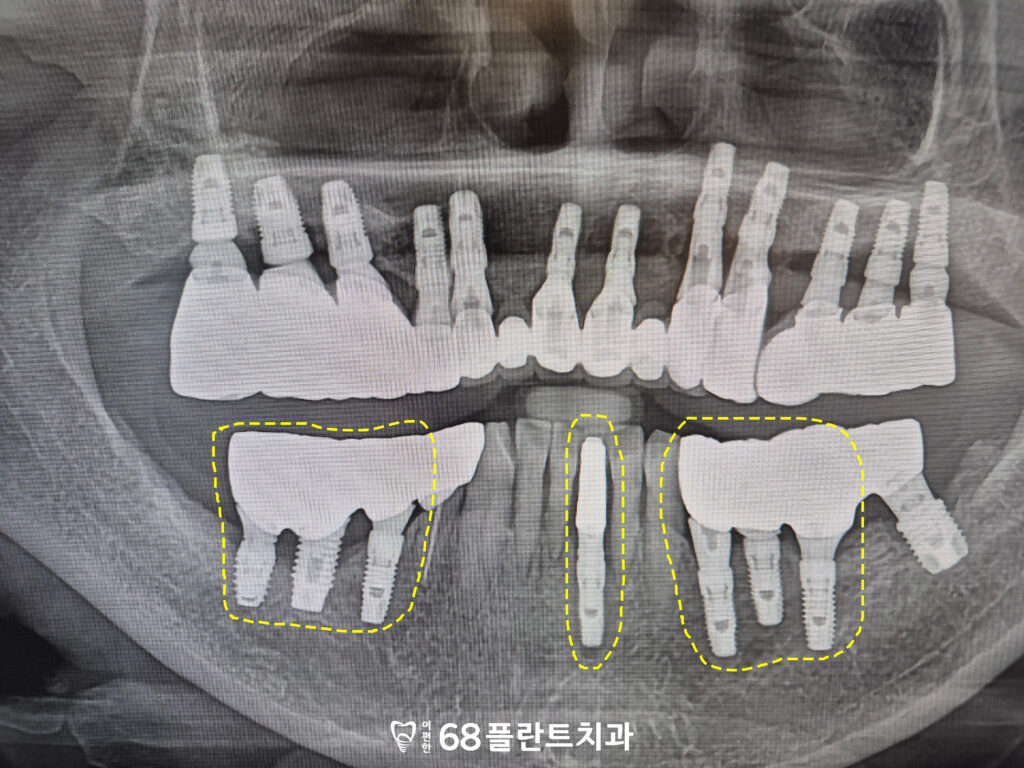

그리고 아래쪽도 잇몸뼈가 부족하고

예후가 불량했던 부위를 전부 발치한 뒤,

임플란트를 식립하여

기능적인 회복을 도모했습니다.

발치 후에는 뼈 이식을 통해

잇몸뼈의 소실된 부분을 보충하고,

이를 바탕으로 임플란트를

안정적으로 식립할 수 있도록 했습니다.

이렇게 임플란트를 식립함으로써

잇몸뼈가 부족했던 부위도

다시 기능을 회복할 수 있었고,

전체적인 치료의 안정성과

장기적인 유지 가능성을

높일 수 있었습니다.

그리고 아래쪽도

임플란트의 치유기간을 거친 뒤

최종 보철 작업 후 마무리 하였습니다.

◆ 전 > 후 ◆

치료 마무리 후 사진입니다.